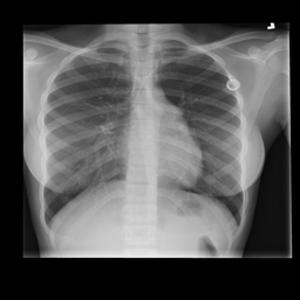

Ushbu platforma ko‘krak qafasi rentgen tasvirlarini sun’iy intellekt yordamida tahlil qilishga mo‘ljallangan bo‘lib, COVID-19, o‘pka fibrozlari, pnevmoniya hamda sog‘lom o‘pka to‘qimalarini to‘rt sinf bo‘yicha aniqlash uchun maxsus o‘qitilgan konvolyutsion neyron tarmoq (CNN) modelidan foydalanadi. Tizim tasvirni oldindan qayta ishlash, shovqindan tozalash va kontrastni kuchaytirish kabi raqamli algoritmlar asosida yuqori aniqlikdagi diagnostik xulosani taqdim etadi.